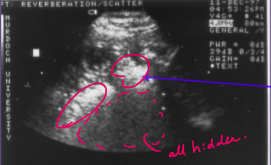

a. Name this type of artifact?

b. What caused it?

a. This is a reverberation artefect

b. This is caused by a junction between soft tissue and air